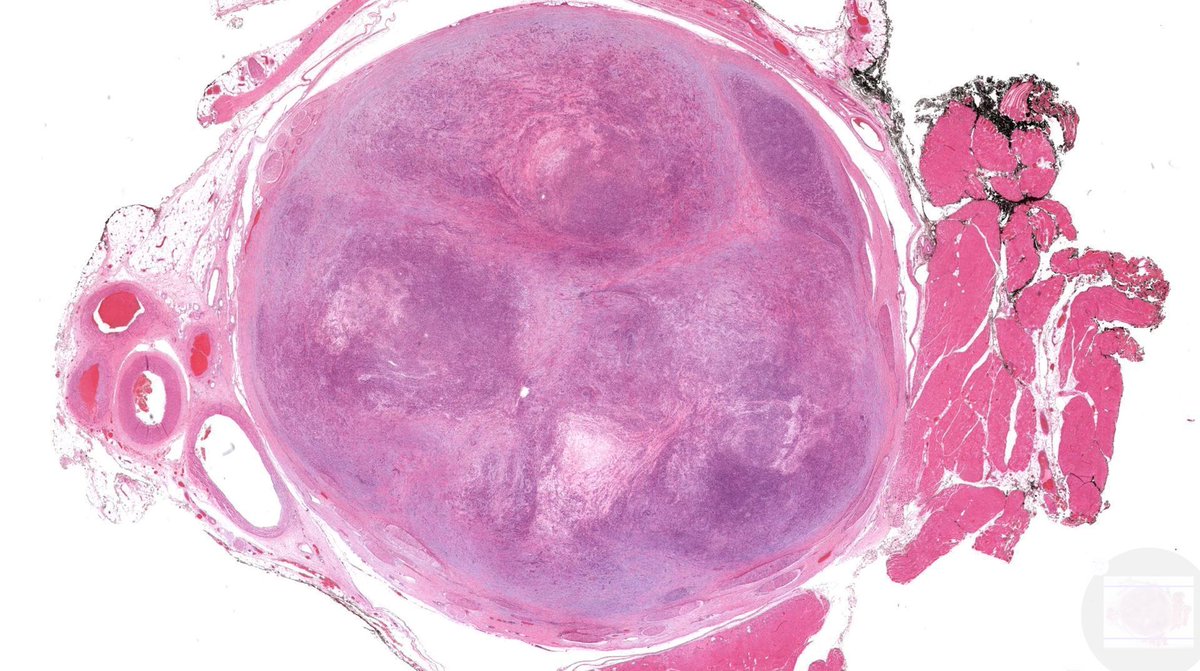

Tristan Rutland MBBS FRCPA IFCAP@TristanRutland7·

🔬𝐓𝐫𝐢𝐩𝐥𝐞-𝐍𝐞𝐠𝐚𝐭𝐢𝐯𝐞 𝐁𝐫𝐞𝐚𝐬𝐭 𝐂𝐚𝐫𝐜𝐢𝐧𝐨𝐦𝐚 (𝐍𝐒𝐓) 🔬 ⚠️ Pitfall alert 1️⃣ TNBCs can exhibit a range of morphologies, from metaplastic (sometimes resembling salivary gland tissue) to poorly differentiated or undifferentiated forms. 2️⃣ DCIS is usually absent. 3️⃣ GATA3 may be lost 4️⃣ SOX10 is usually positive (mimic melanoma). 5️⃣ 𝐃𝐢𝐚𝐠𝐧𝐨𝐬𝐭𝐢𝐜 𝐓𝐢𝐩: Always do a keratin and review patients history! #Breastpath #Dermpath #Pathtwitter #Pathresidents

Tristan Rutland MBBS FRCPA IFCAP tweet mediaTristan Rutland MBBS FRCPA IFCAP tweet mediaTristan Rutland MBBS FRCPA IFCAP tweet mediaTristan Rutland MBBS FRCPA IFCAP tweet media